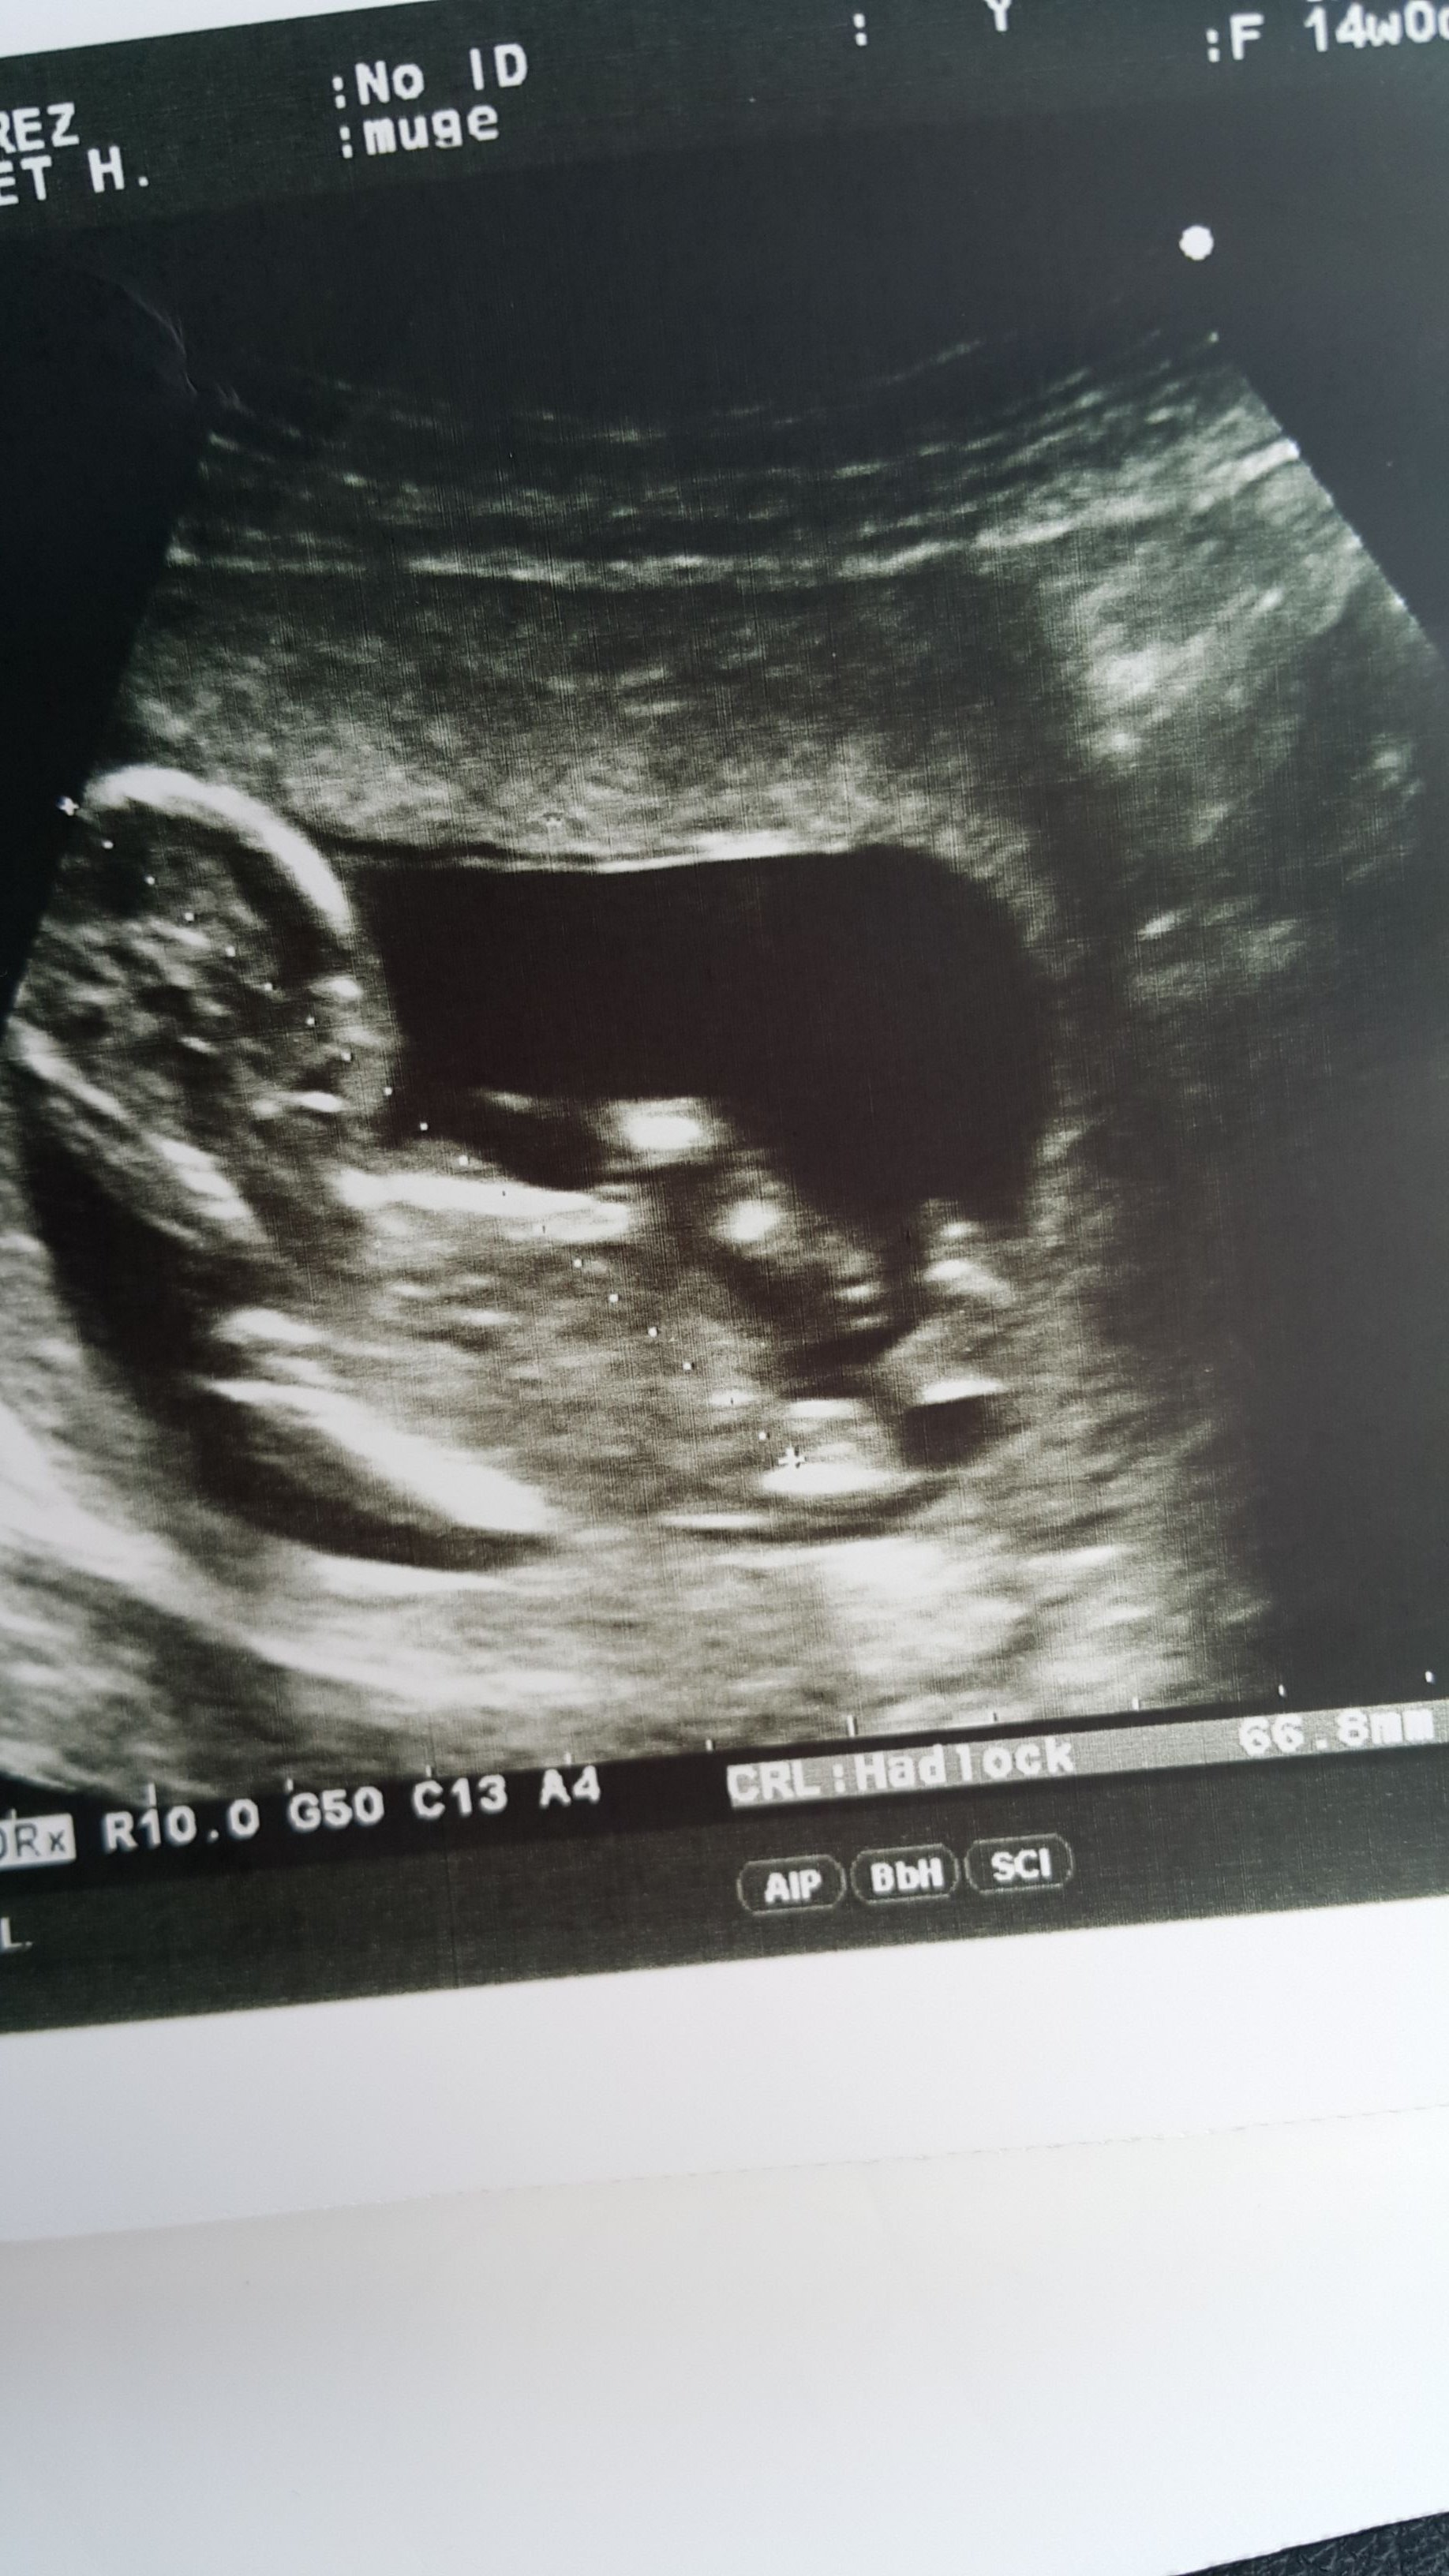

Sizce benim bebişimin cinsiyeti ne olabilir

IMG-20170125-WA0012.jpeg